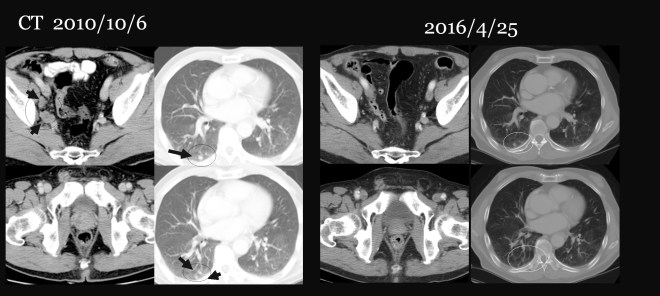

이번 원고에서 소개하려는 환자는 74세의 남성으로, 2010년 10월 전립선암 4기 골반벽전이 폐전이(prostatic cancer IV stage  with lung metastasis)로 아산병원에서 진단을 받았다. 초기에   bicalutamide(상품명 casodex)를 복용하면서 초기에 GnRH agonist인 zoladex 주사를 한차례 시행하였다. 그리고  2010년 11월 초에 반룡인수 clinic으로 방문하였다.

이 환자는 당시 검사로 4기 폐전이 진단을 받았고, 주치의는 암의 상태가 현재 사용하고 있는     protocol로 1년 정도 억제시켜 줄 수 있지만, 1년이 넘으면 약이 안 들을 것이라고 하였다. 그래서 장기생존이나 완치에 대한 여부는 불투명하다고 들었다. 이같이 주치의 한테서 안 좋은 예후에 대한 설명을 듣고 나자 다른 방법을 찾아서 나의 clinic을 방문하였다. 그래서  2010년부터 2013년까지 나의 방법대로 한약과 양약을 결합하여서 치료를 하였다. 그리고 전립선암은 완치 판정을 받았다. 그리고 한약을 끊고 나서 이 환자는 주로 태국에 가서 살았는데 2014 년 3월 아주 조기위암 (early stage stomach cancer)로 진단을 받았다. 조기위암에 대해서는 수술을 받았다. 별다른 항암이나 방사선 조치는 받지 않았다. 그리고  2017년까지 전립선암이나 위암에 대한 재발이 없이 지내고 있다. 2014년이후에는 이 환자는 한약으로 전립선암을 치료할 때처럼 식이요법을 철저히 지키지는 못하였던 것으로 안다. 환자부부가 고령이라, 남이 해주 는 밥을 먹고, 직접다이어트 식단을 챙겨 먹지 못하였다. 그리고 인도네시아 태국에서 일년의 대부분을 지내고 있었다. 이러한 환경이 아마도 다시금 위암을 생기게 하였으리라고 본다. 다행히 조기수술을 받고서 위암도 완치가 되었다. 그래서 이번 원고에서는 이 환자의 치료과정을 소개하면서, 암을 자라게 한 환경과 나의 새로운 protocol의 치료효과를 설명하려고 한다.

2010/10/6  CT 복부와 골반부

• 조직검사로 입증된 전립선암

• 우측obturator muscle, 우측 external, common iliac, paraaortic, retrocavla and retrocrural 부위의 림프절 전이

• 우측 폐의 하엽의 뒷벽에 전이로 보이는 폐의 덩어리들

• 신장에 4cm에 이르는 단순 양성 물혹

• 골반에 양성으로 보이는 뼈의 이상 부위

2010/10/14  CT 가슴사진

• 여러 개의 작은 RML(우측중엽)과 RLL(우측 하엽)의 덩어리들로 전이로 보인다.

• 우측 빗장뼈 위로 1.6cm 가량의 커져 있는 림프절이 보인다. 아마도 전이로 보인다.

• 왼쪽의 신장에 물혹

• 특별한 흉추의 뼈의 이상은 보이지 않음

당시 환자의 CT를 간략하게 소개해 본다.

정영기1-2.jpg

• 우측 폐의 우측 하엽에 보이는 하얀 점들(검은 화살표)이 폐전이 된 암임

• 전립선은 비대되어 있다.

• 좌측 골반뼈 주위에 림프절 전이(검은 화살표)가 보인다.

1-3.jpg

이 환자는 당시 1년 이상 치료를 한 후에 골반벽과 복부에 있는 임파절이 다 없어졌고 폐에도 multiple 하게 보이던 종양이 소실되었고 위에 사진에 보듯이 우측 하엽에 보이던 종양도 소실이 되어서 전립선암 완치 판정을 받았다. 이전 CT가 여러 군데 흩어져 잘 찾아지지 않아서, 여기서는 2016년도 신세포암을 발견하고 가져왔던 사진으로 비교를 해 본다. 위의 사진(2016/4/25)을 보면 전립선의 크기도 현저히 줄어들었다. 이전의 골반벽림프절들은 모두 소실이 되었다.

정영기1-5.jpg

이분은 2014년 한약을 중단하고 나서  1년 지나서 위장에 매우 초기 종양이 발견되어서 수술로 제거하고, 방사선이나 약물치료 없이 추적관찰 중이었는데  2016년도에 또다시 신장에 신세포암이 발생하였다.  2014년 이후에는 본원의  치료를 받지 않았지만 위암은 무사히 지나갔고,  2016년 4월 사진에서 좌측 신장에 작은 암이 발견되어서 복강경으로 제거를 하였다.

환자는 전립선암은 마쳤지만 다시 위암이 발생하고  또 위암은 끝났는데 연이어 신세포암이 발생하여서 아직 투병이 끝나지 않은 상태에서  2017년도 3월에 CT를 가지고 찾아왔다. 이전에 전립선암 때 한때 다 사라져서 보이지 않았지만 , 2017년 C 에서는 매우 미세한 nodule들이 폐에 몇 개 보였는데, 나름대로 생각이 있어서 그런지 한방치료를 택하지는 않았다. 이 신장에 보이는 작은 종양은 위에서 보듯이  2016/4/25일 검사에서 신세포암일 가능성을 시사하였고, 위벽이나 위 혹은 복부에 다른 임파절은 없다는 설명이다. 이전 전립선암 때 열거되었던 수많은 복부와 골반벽임파는 다 소실이 되었고  폐에 위의 사진에서 보듯이 작은 점이 하나 남아있는데, 이는 양성인 granuloma로 보인다는게 아산병원의 그간 추적의 소견이다. 이 환자도 중간 과정을 CT를 찾아보니 다른 콤퓨터에 흩어져 있어서 바로 1년 뒤에 소실되었을 때를 비교해서 시를 못한다. 그래서 2016년도 복부사진을 통해서 초기 2010년 사진과 비교해 보았다. 이를 보면 이전 종양들은 다 사라진 것을 알 수 있을 것이다.